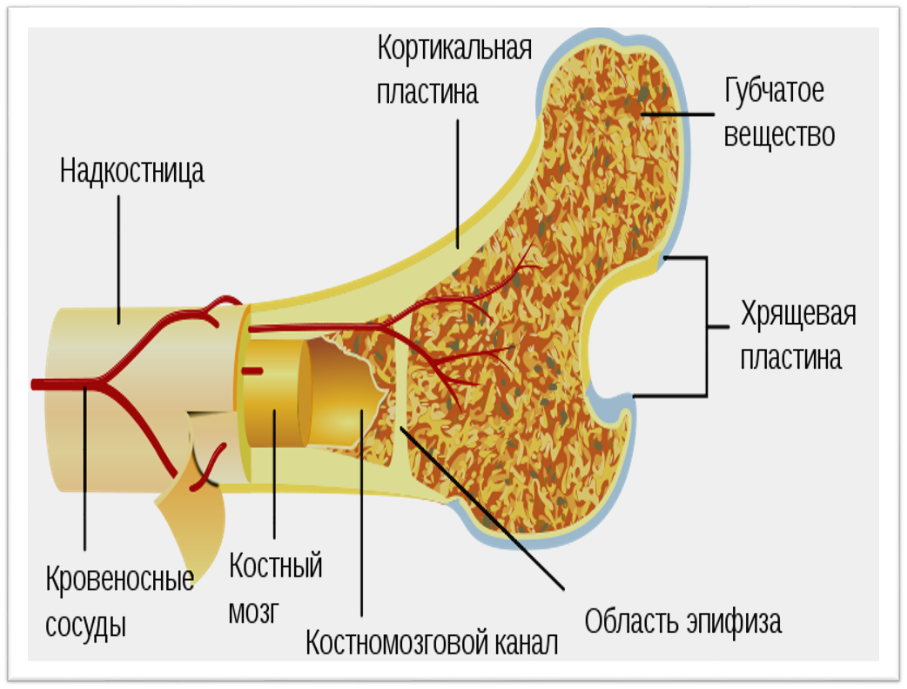

Изучение костного мозга: анатомия и функции